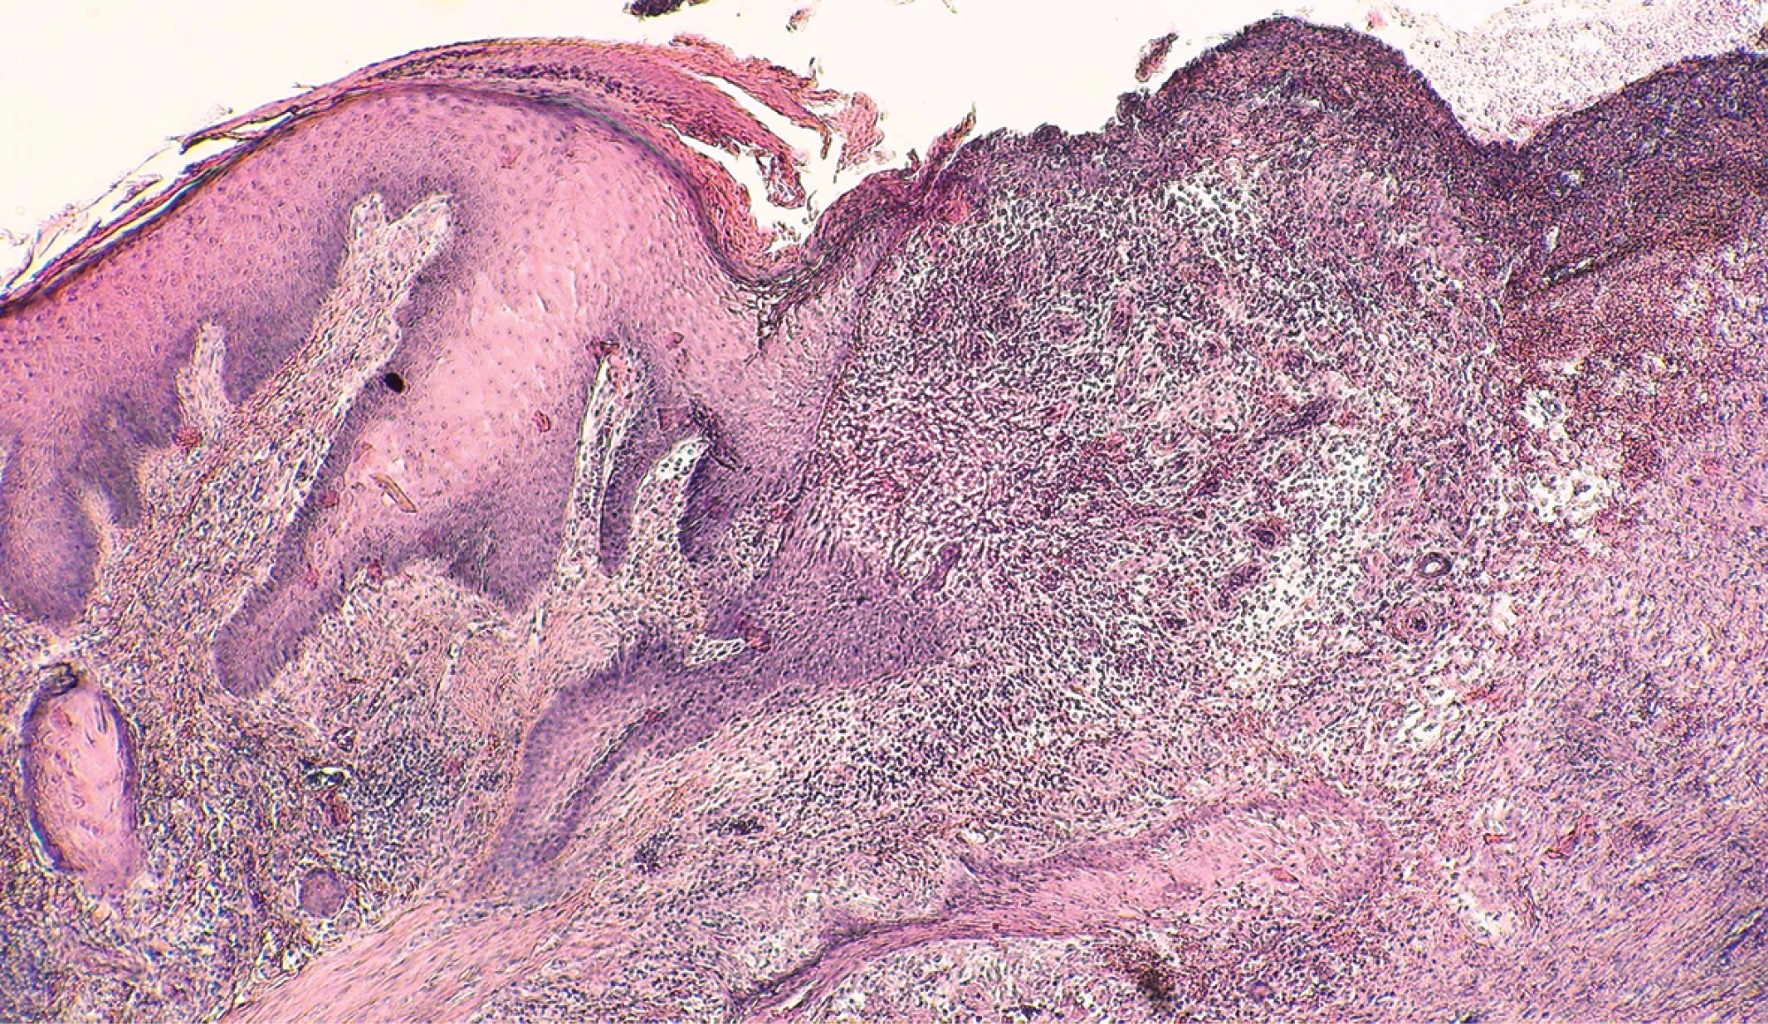

Los hallazgos histopatológicos no son característicos de PG; en las lesiones iniciales aparece una reacción vascular neutrofílica que puede ser foliculocéntrica. Los infiltrados neutrofílicos se observan en las lesiones activas, con necrosis central, ulceración de la epidermis y escaso infiltrado mononuclear más periférico, engrosamiento del endotelio capilar, hemorragia y coagulación. Los hallazgos histopatológicos también dependen del sitio de la biopsia (borde, centro o área necrótica de la úlcera), el estadio de progresión y la variedad de la enfermedad (vegetante, ampollosa, ulcerosa o pustulosa).8

Entre sus antecedentes patológicos refirió artritis reumatoide sin tratamiento de ocho años de evolución, tabaquismo con índice tabáquico de 3.75 y alcoholismo positivo a razón de 10 copas semanales hasta llegar a la embriaguez. Se solicitan estudios de laboratorio generales sin encontrarse datos relevantes, el factor reumatoide fue de 9.6. Dentro del protocolo de estudio se realizó una biopsia incisional de piel para estudio histopatológico, el cual mostró la epidermis con acantosis regular, zonas con hiperplasia pseudoepiteliomatosa, amplias zonas ulceradas. La dermis superficial, media y profunda mostró infiltrados moderadamente densos con participación de histiocitos, células gigantes multinucleadas de tipo cuerpo extraño, así como numerosos polimorfonucleares dentro y fuera de los vasos; amplias zonas de fibrosis de la colágena y focos con extravasación de eritrocitos (Figuras 5, 6 y 7).